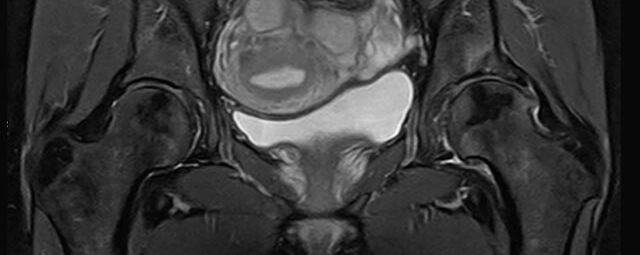

• Urogenitalorgane

• Tumordiagnostik z.B. im Bereich der Ovarien, des Uterus, der Prostata oder Harnblase

• dynamische MR-Analyse bei Beckenbodeninsuffizienz

MRT der Prostata

Durchführung dieser Untersuchung nur an den Standorten am Diakonissenkrankenhaus und am Markkleeberg-Center

Die multiparametrische MRT (mpMRT) der Prostata ist ein modernes, strahlungsfreies Verfahren zur Früherkennung und Abklärung von Prostatakrebs. Sie kombiniert verschiedene MRT-Techniken (T2, DWI, DCE) und ermöglicht eine präzise Darstellung verdächtiger Areale. Laut aktuellen Leitlinien der Deutschen Röntgengesellschaft und Deutschen Gesellschaft für Urologie ist sie der empfohlene Standard bei erhöhtem PSA-Werten, vor Biopsien oder bei unklaren Vorbefunden.

Im Vergleich zur klassischen Ultraschallbiopsie erkennt die mpMRT klinisch relevante Tumoren zuverlässiger und hilft, unnötige Eingriffe zu vermeiden. Die Untersuchung ist schmerzfrei und dauert etwa 30–45 Minuten.

Wir führen die mpMRT der Prostata an unseren Praxisstandorten für ausgewählte Kassenpatienten, Privatpatienten und Selbstzahler durch – mit Befundung nach PI-RADS v2.1 durch erfahrene Radiolog*innen. Vereinbaren Sie gern einen Termin!